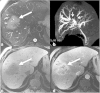

Malignancies of the biliary tract include cholangiocarcinoma, gallbladder cancers and carcinoma of the ampulla of Vater. Biliary tract adenocarcinomas are the second most common primary hepatobiliary cancer. Due to their slow growing nature, non-specific and late symptomatology, these malignancies are often diagnosed in advanced stages with poor prognosis. Apart from incidental discovery of gall bladder carcinoma upon cholecystectomy, early stage biliary tract cancers are now detected with computed tomography (CT) and magnetic resonance imaging (MRI) with magnetic resonance cholangiopancreatography (MRCP). Accurate characterization and staging of these indolent cancers will determine outcome as majority of the patients' are inoperable at the time of presentation. Ultrasound is useful for initial evaluation of the biliary tract and gallbladder masses and in determining the next suitable modality for further evaluation. Multimodality imaging plays an integral role in the management of the biliary tract malignancies. The imaging techniques most useful are MRI with MRCP, endoscopic retrograde cholangiopancreatography (ERCP), endoscopic ultrasound (EUS) and positron emission tomography (PET). In this review we will discuss epidemiology and the role of imaging in detection, characterization and management of the biliary tract malignancies under the three broad categories of cholangiocarcinomas (intra- and extrahepatic), gallbladder cancers and ampullary carcinomas.